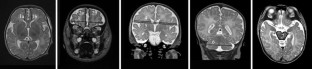

Infants with congenital heart disease (CHD) have delayed brain maturation and alterations in brain volume. Brain metrics is a simple measurement technique that can be used to evaluate brain growth. This study used brain metrics to test the hypothesis that alterations in brain size persist at 3 months of age and that infants with CHD have slower rates of brain growth than control infants. Fifty-seven infants with CHD underwent serial brain magnetic resonance imaging (MRI). To evaluate brain growth across the first 3 months of life, brain metrics were undertaken using 19 tissue and fluid spaces shown on MRIs performed before surgery and again at 3 months of age. Before surgery, infants with CHD have smaller frontal, parietal, cerebellar, and brain stem measures (p < 0.001). At 3 months of age, alterations persisted in all measures except the cerebellum. There was no difference between control and CHD infants in brain growth. However, the cerebellum trended toward greater growth in infants with CHD. Somatic growth was the primary factor that related to brain growth. Presence of focal white matter lesions before and after surgery did not relate to alterations in brain size or growth. Although infants with CHD have persistent alterations in brain size at 3 months of age, rates of brain growth are similar to that of healthy term infants. Somatic growth was the primary predictor of brain growth, emphasizing the importance of optimal weight gain in this population.

Fig. 1